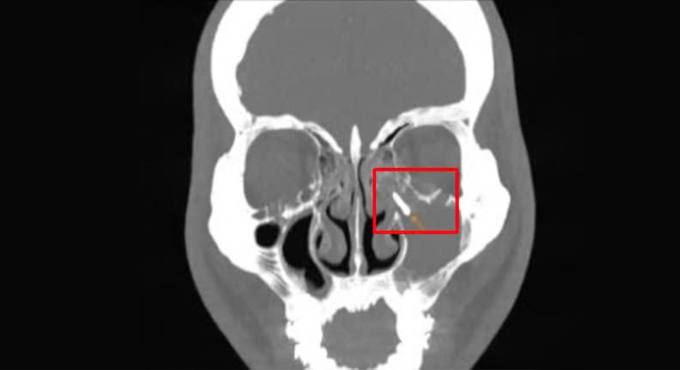

Kết quả cho thấy tổn thương lấp đầy xoang hàm trái, xơ đặc thành xoang, tắc lỗ thông xoang, có dị vật kim loại bên trong xoang. Đồng thời, các chân răng 15, 16, 17 lồi sát vào xoang hàm, dày nhẹ niêm mạc xoang hàm.

Chụp CT cho thấy dị vật ở xoang hàm bên trái của anh Phú. Ảnh: Bệnh viện Đa khoa Tâm Anh